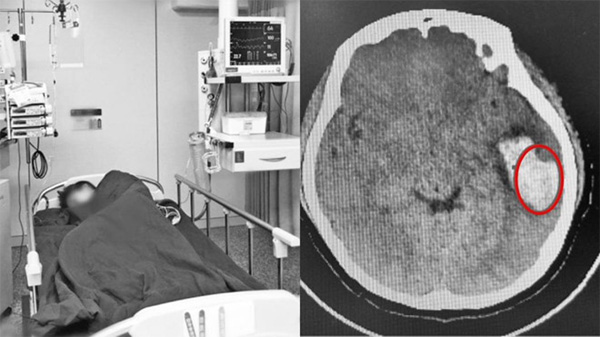

Cô được bạn bè đưa ngay đến Bệnh viện Đại học Trịnh Châu (Hà Nam, Trung Quốc) để cấp cứu. Kết quả chụp CT cho thấy mạch máu não của Hoan Hoan bị vỡ. Các bác sĩ còn phát hiện lượng lớn máu chảy ra, chèn ép vào các tổ chức não bộ, dây thần kinh. Đây là nguyên nhân trực tiếp dẫn đến việc cô cảm thấy buồn nôn và chóng mặt.

Nữ sinh Hoan Hoan vỡ mạch máu khi hát karaoke, phải điều trị tại bệnh viện. Ảnh: hk01.

Hoan Hoan được mổ cấp cứu để lấy khối máu tụ trong não, đề phòng biến chứng. Cô được theo dõi liên tục trong 72 giờ sau mổ cho đến khi đảm bảo không còn nguy cơ xảy ra biến chứng về não.